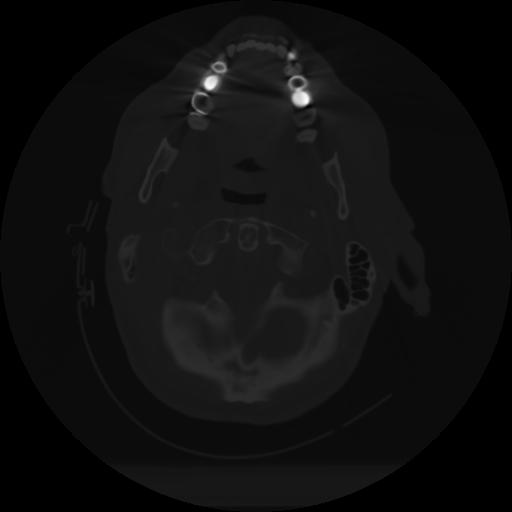

10 P.BLANDAS,,Axial,2.0,P.BLANDAS,,